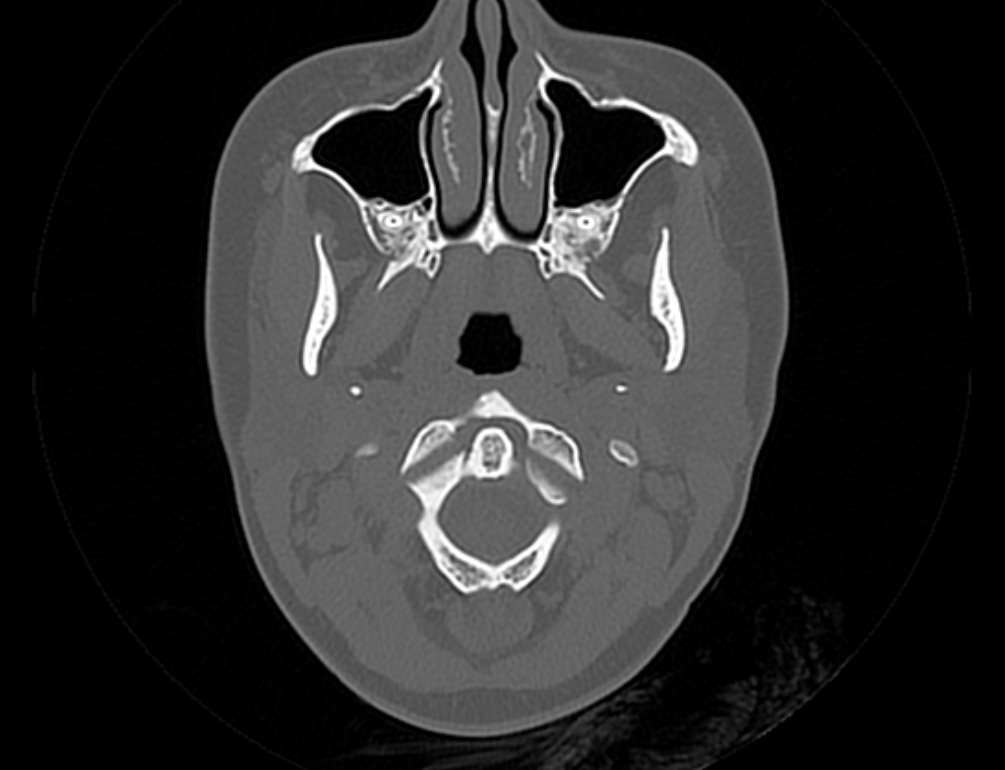

Мультиспиральная компьютерная томография является наилучшим методом диагностики патологии костей черепа. В основе методики лежит использование рентгеновского излучения с последующей цифровой обработкой полученных данных и получения трехмерных реконструкций изображений.

Костная ткань отличается высокой плотностью и способна в большой степени поглощать рентгеновские лучи. Поэтому на послойных снимках, полученных при проведении мультиспиральной КТ черепа можно детально рассмотреть свод черепа, кости лица, основание черепа. Это позволяет с наибольшей точностью визуализировать различные объемные образования, такие как остеомы, дифференцировать фиброзную дисплазию или костные метастазы. Преимуществами методики КТ является отличная визуализация костных структур, быстрота выполнения процедуры и доступная цена. Все это делает КТ незаменимой при диагностике травматических повреждений (например переломов основания черепа или орбит), аномалий развития, при планировании оперативных вмешательств.

Что показывает КТ черепа

- наличие чужеродных предметов;

- скрытые переломы;

- смещение костей;

- опухоли как доброкачественные, так и злокачественные

- нарушенное кровообращение;

- воспалительные заболевания

- метастазы и их локализацию